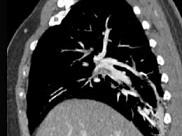

- 单项选择题男,56岁, 食管癌术后,胸痛, 呼吸困难,结合CT图像, 最可能的诊断是 ( )

A、食管癌肺转移

B、肺栓塞

C、支气管扩张

D、肺水肿

E、肺不张